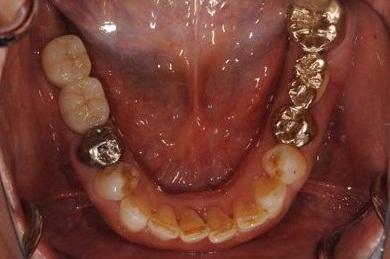

| 性別/年齢 | 女性 / 59歳 | ||||||||||||||||||||||||||||||||

| 主訴 | 奥歯がないので、インプラントか入れ歯の相談をしたい。 | ||||||||||||||||||||||||||||||||

| 治療内容 | インプラント4本(GBR)、ハイブリッドセラミック4本 | ||||||||||||||||||||||||||||||||